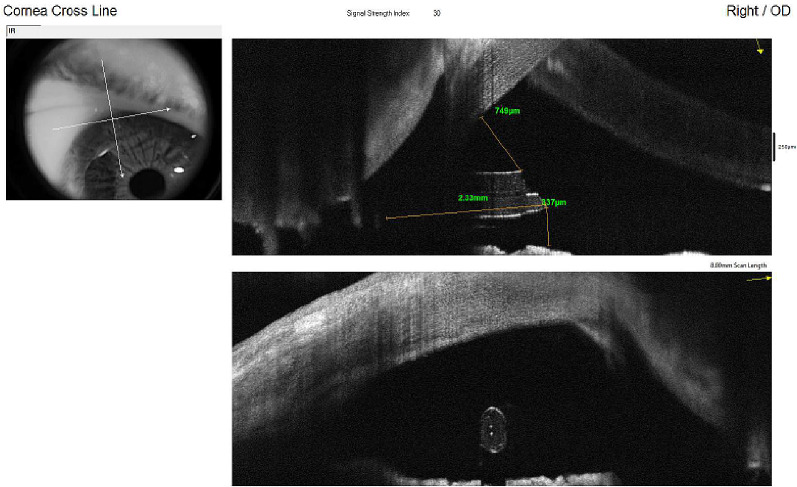

During postoperative visits, these measurements were repeated while accounting for the central ECD. During follow-up, anterior segment optical coherence tomography (AS-OCT) with the Avanti Widefield (Optovue, Inc., Fremont, CA, USA) was used to evaluate the distance of the tube from the endothelium and iris and its length in the AC using the caliper tool of the “Crossline” option. Measurements from the distal superior end of the beveled tip of the tube were performed perpendicular to the internal surface of the cornea (tube–endothelium [TE] distance) [5], and from the distal inferior end of the tube to the iris plane (tube–iris [TI] distance) (Fig. 1). These measurements were repeated at 1 week and at 1, 3, 6, and 12 months after surgery.

Fig. 1.

AS-OCT image of the tube of the PRESERFLO in the AC. The caliper tool of the “Crossline” software of the Optovue Avanti Widefield was used to measure the distance from the tube to the endothelium and the iris and its total length

The length of the tube in the AC was measured from the beveled tip to the angle at 3 months (Fig. 1). Peripheral anterior synechiae (PAS) were evaluated by AS-OCT (Fig. 2).